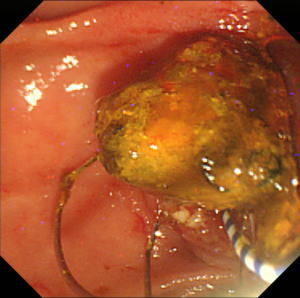

| 【大腸ESD】 |

直腸の半周近くを占める早期の直腸癌。癌の範囲をわかりやすくするためインジゴカルミンという青い色素を散布してあります。 |

Hook knifeという粘膜下層剥離術専用の電気メスを用いて癌のすぐ下の層を剥離しています。大腸や直腸は消化管の壁が非常に薄いため、穿孔(腸壁に穴を開ける)させないように注意深く剥離を進めます。 |